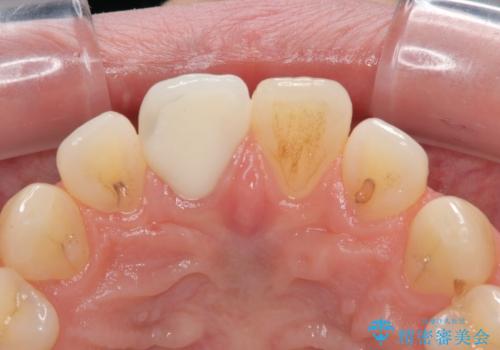

隣の歯と色が調和して、自然な仕上がりで満足されました。